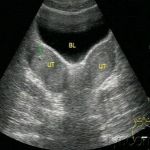

副中肾管衍生物发育不全所致异常,就会发生子宫和输卵管发育异常,如无子宫、无阴道、始基子宫、子宫发育不良、单角子宫等,而副中肾管衍生物再造障碍,则会导致双子宫、双角子宫、鞍状子宫和纵隔子宫等发育异常。